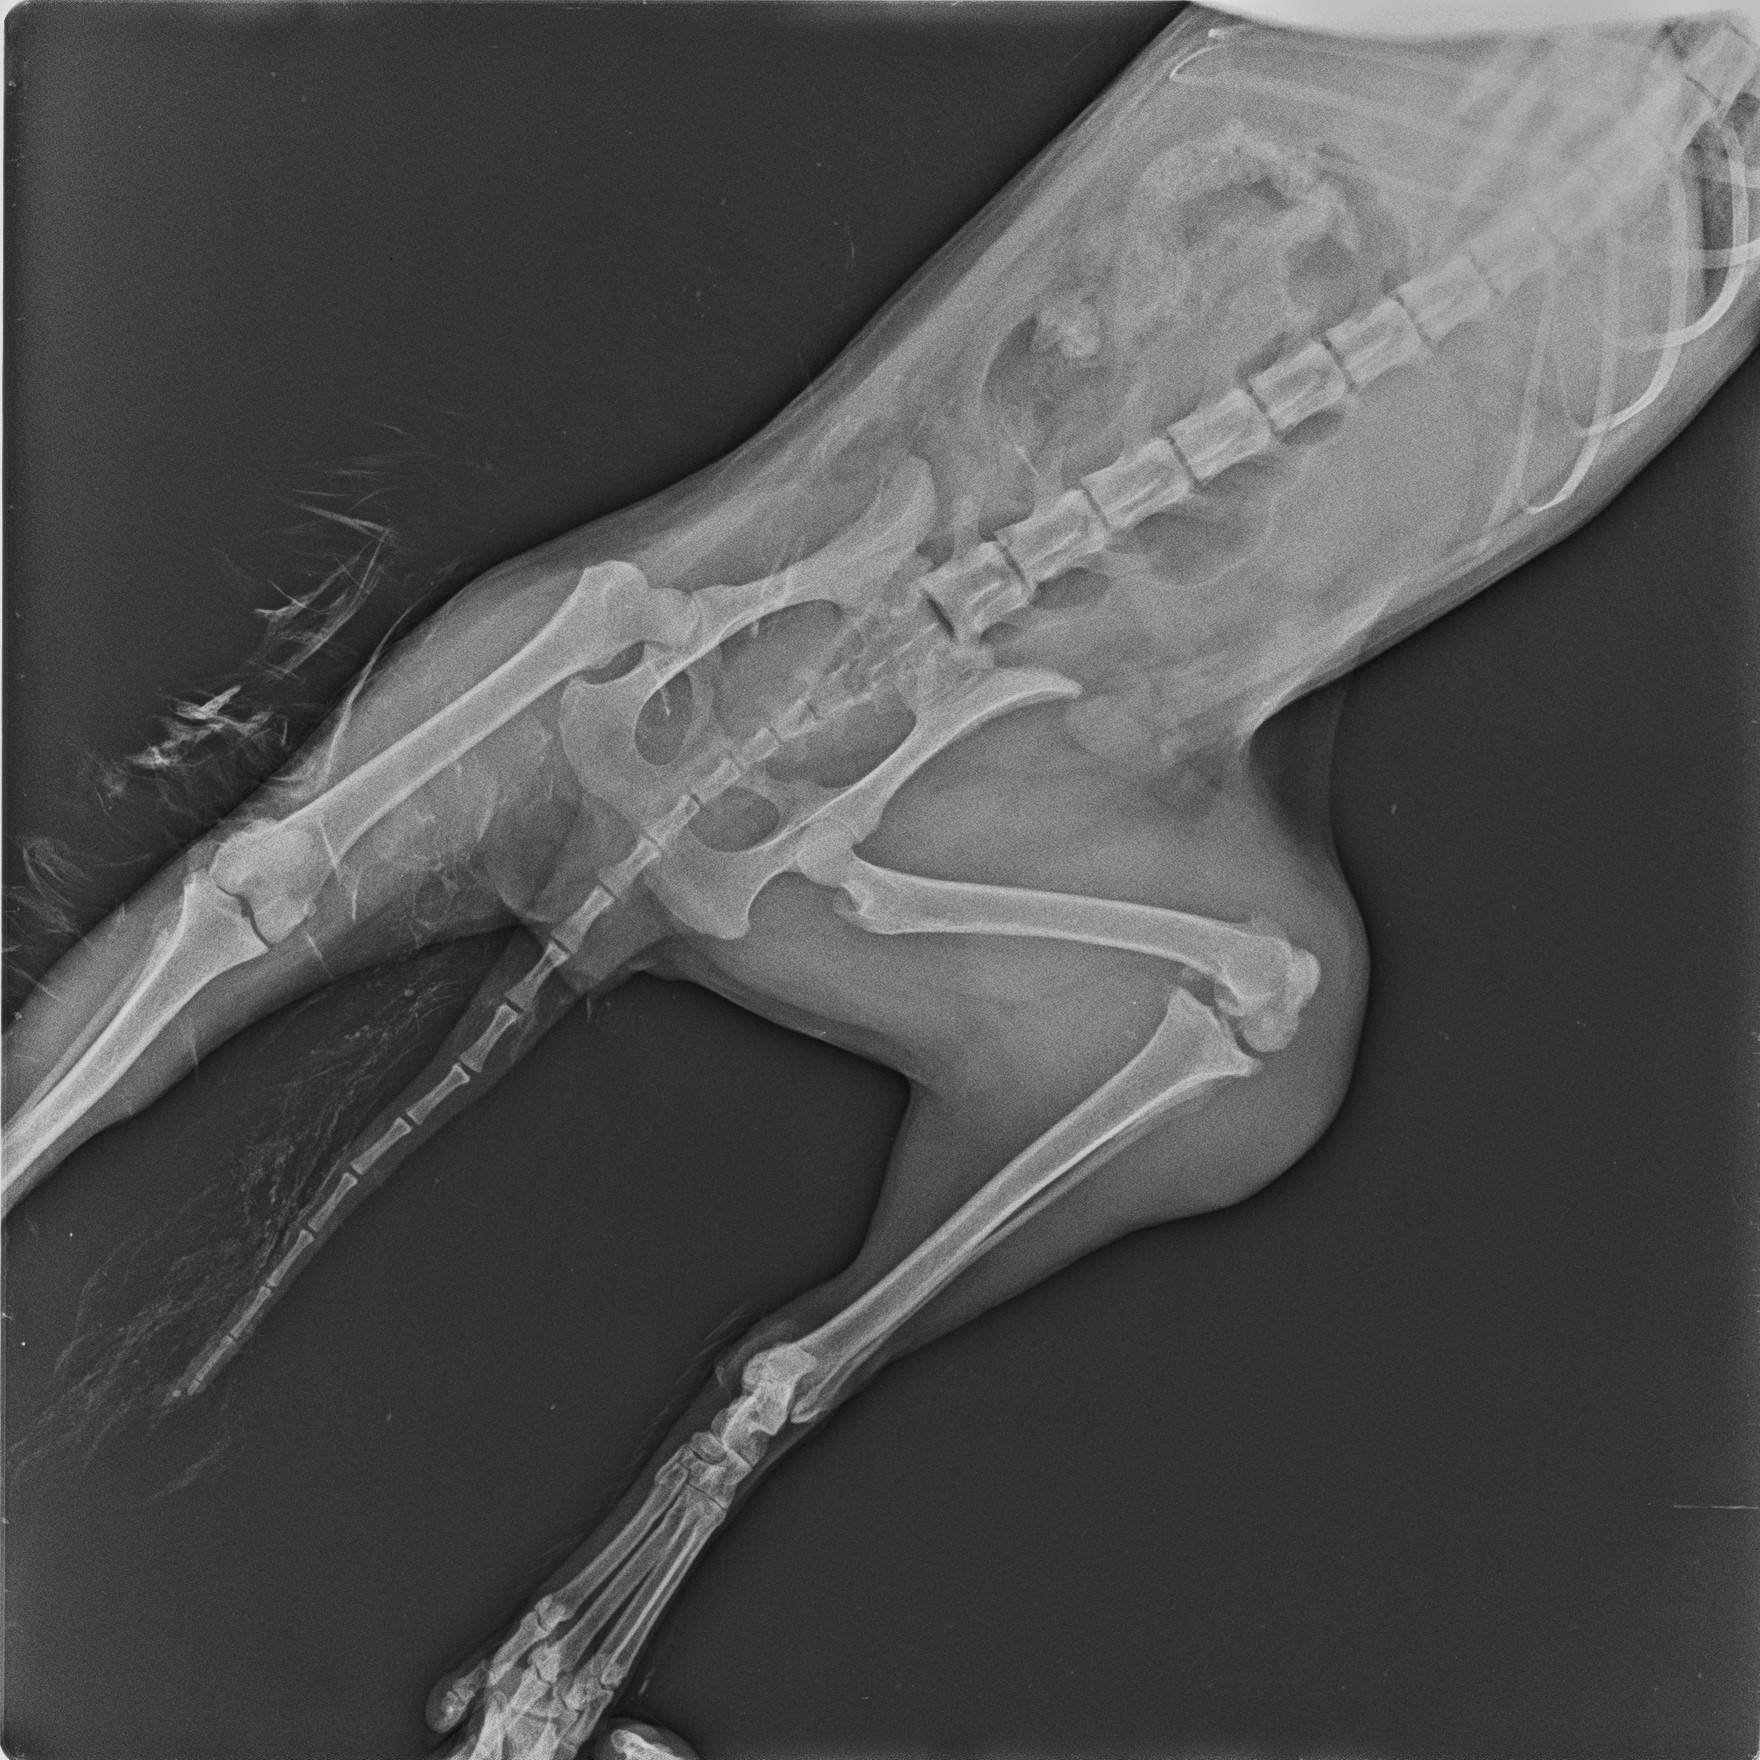

その際撮ったレントゲン写真がこちらです。

骨折は見当たらなかったものの、左後肢の膝関節がものすごく腫れていました。

あまりに腫れているので、そのときは動かすこともできませんでした。

そして腫れて動かなかった左後肢の膝関節がグラグラしているのを認め、脱臼していることがわかりました。